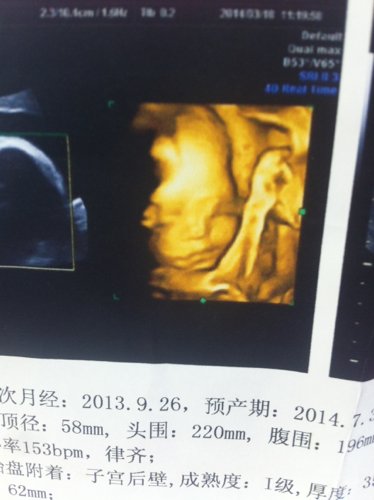

帮忙看下这两张是怀孕24周做的四维彩超图,感觉鼻子和眼睛有问题、你们认为有什么问题吗? 点击展开 匿名用户 2014-04-04 16:57 为您推荐: 其他回答 病情分析: 你好,根据你描述的看没有看到什么地方有异常表现,具体发育是否有问题要看b超结果来确定的。 指导意见: 如果结果都是正常的就不用担心的,照片的情况因为有羊水所以看到不是很清晰是没有关系的,希望对你有帮助,祝你健康幸福 郎文曜_gkBv 2014-04-04 17:00 相关问题 这是24周做的四维彩超图,帮忙看下图片有问题吗?我怎么感觉鼻子和眼睛怪怪的,好担心 我怀孕24周了鼻子一投就躺血这是为什么 孕妇怀孕八周了、这两天鼻子出血是什么情况、要不要紧